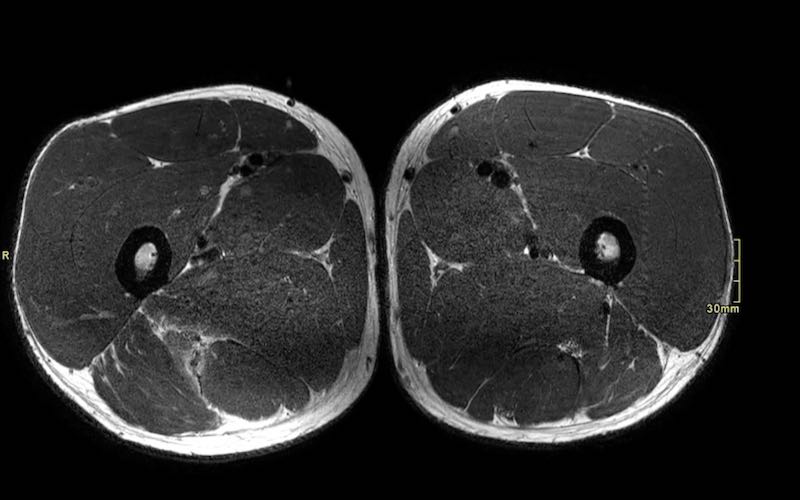

Trên các hình ảnh axial này, có thể thấy tăng tín hiệu và dày lên của gân cơ nhị đầu đùi bên trái (vòng tròn chấm vàng) khi so sánh với bên không bị tổn thương (vòng tròn chấm trắng).

Tại đây bạn có thể cuộn qua các hình ảnh axial. Có thể phóng to hình ảnh bằng cách nhấp vào chúng.

Đây là tổn thương bán phần, bắt đầu từ gân chung ở phía gần, bao gồm cả vùng MTJ và gân trong cơ ở phía xa hơn. Chiều dài vùng phù nề và mức độ biến dạng gân đều ở mức độ cao. Trường hợp này được phân loại là tổn thương BAMIC 3b/c.